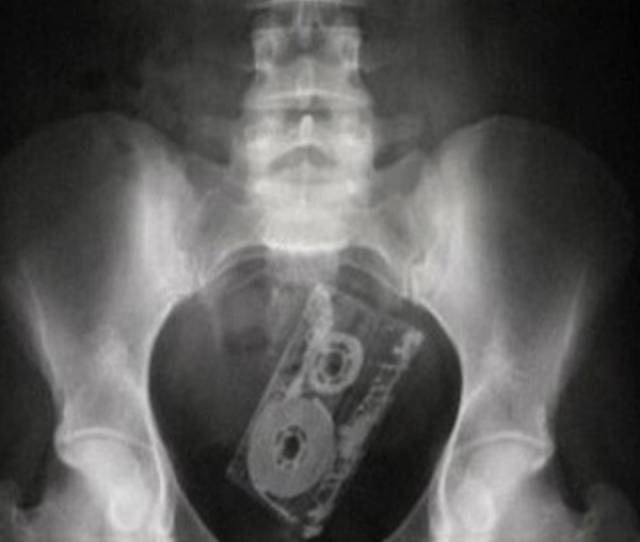

A cell phone.